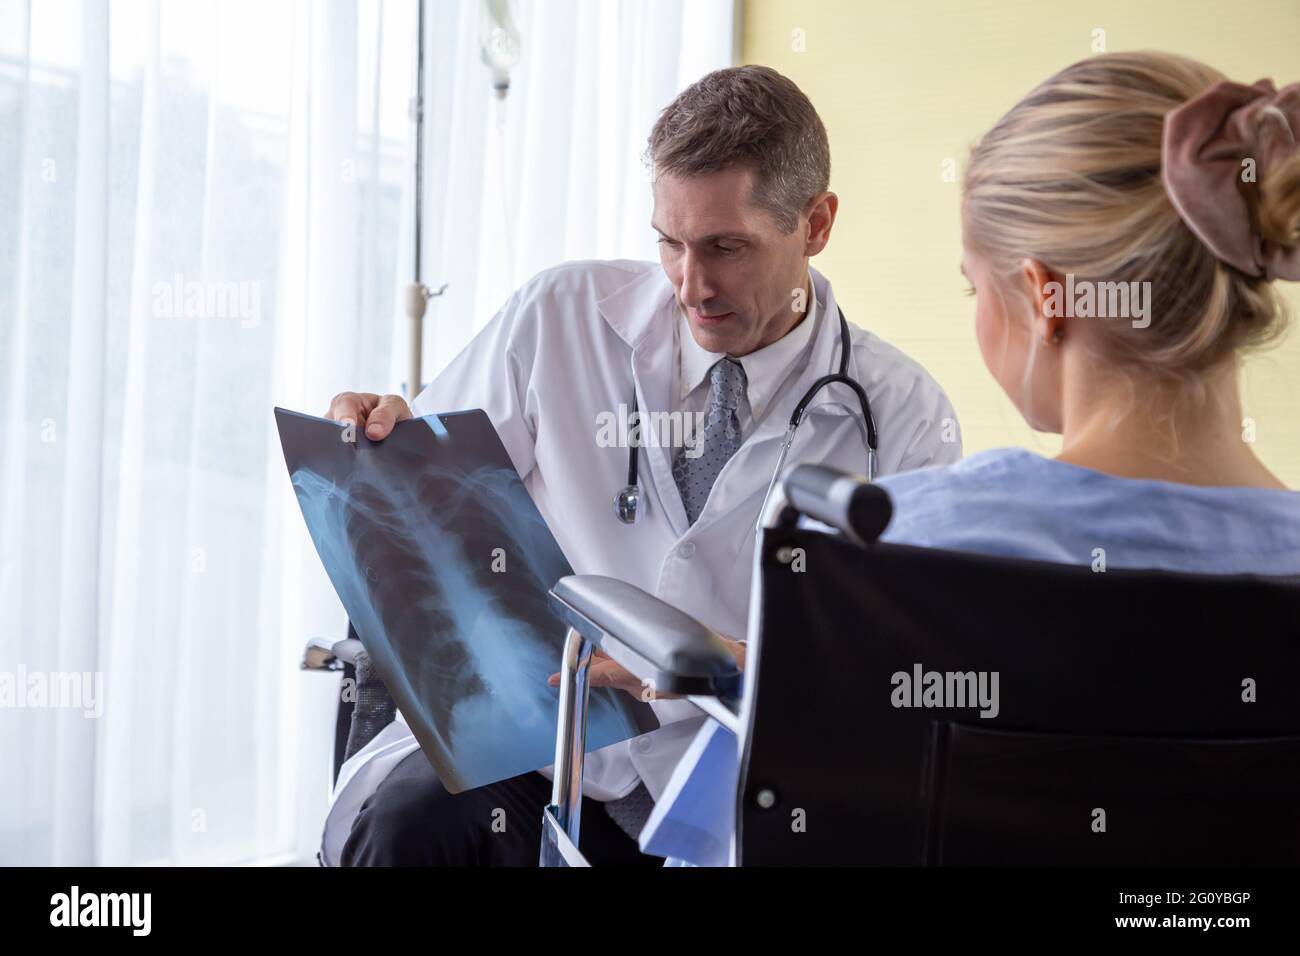

RF2G0YBGP–Médecin examinant le film radiographique thoracique de la patiente à l'hôpital. Concept de symptômes de syndrome respiratoire ou de pneumonie virale

RF2G0YBGW–Médecin examinant le film radiographique thoracique de la patiente à l'hôpital. Concept de symptômes de syndrome respiratoire ou de pneumonie virale

RF2G0YBHA–Médecin examinant le film radiographique thoracique de la patiente à l'hôpital. Concept de symptômes de syndrome respiratoire ou de pneumonie virale